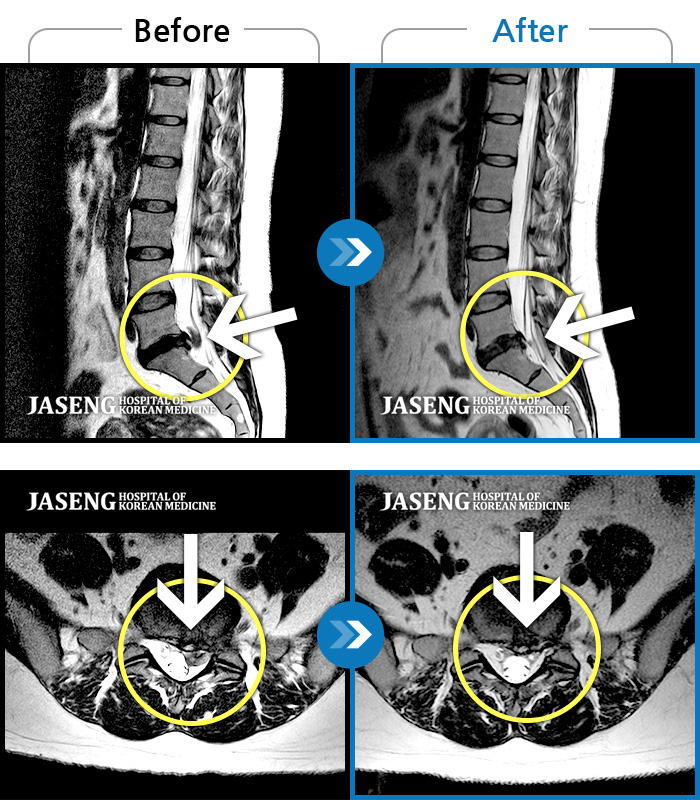

Before

After

통증으로 아기를 안지 못하던 여자분입니다

2023.11.08 ~ 2024.07.29